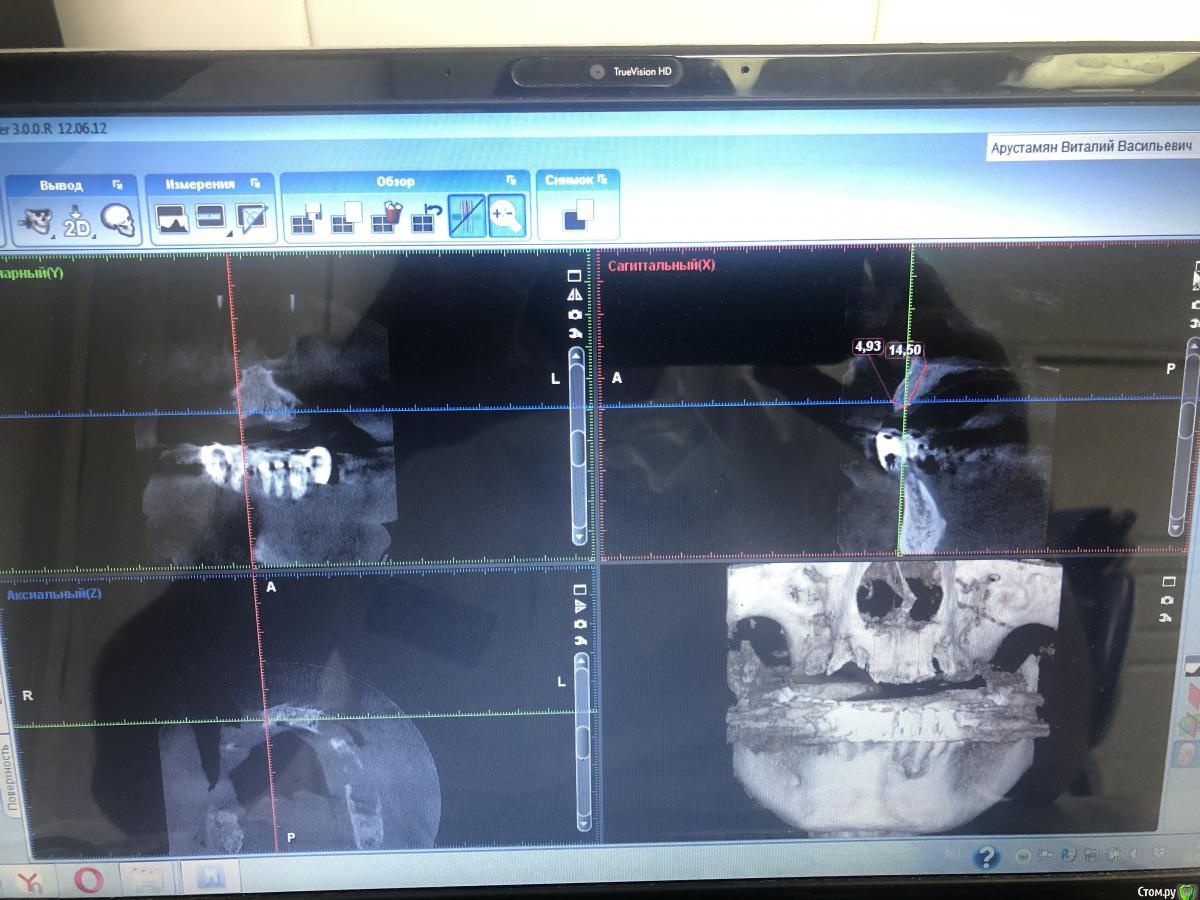

Александр07 Опубликовано 1 июля, 2020 Поделиться Опубликовано 1 июля, 2020 Коллеги доброго дня, пац 55-60 лет, хочет чтобы было красиво и крепко держалось, такая ситуация во рту, планируем операцию на вчКак видите примерно в обл 1.4-1.6 дефект по высоте, размышляю по поводу установки 1.1,1.3, 2.2,2.4 с расщеплением в обл 1.3, под протез на балке, Врем конструкция на импл , даже при условии что получится без большой подсадки, не рискнул бы- крупный мужчина, будет давать нагрузку, если ставить Мини импл то планировал бы позиции 2.1,2.5, 1 сегмент пока не ясно куда ставить ) По аугментации в обл 1.5-1.6, что посоветуете- делать /не делать, одновременно с фронтом или отдельно, или ограничиться тем планом по балке что написал выше , В обл 2.5-2.6 синус нужен trim.F286E467-8CC6-421B-ACE6-47434003E04E.MOV Ссылка на комментарий

Bier Опубликовано 1 июля, 2020 Поделиться Опубликовано 1 июля, 2020 мне не нравится вариант с расщеплением.тут нужно еще КТ покрутить 1 Ссылка на комментарий